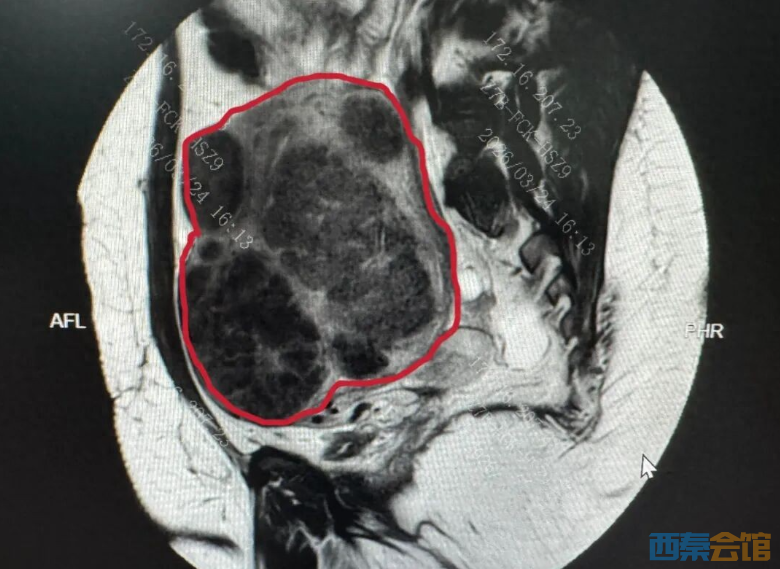

图示PUSH术前MRI子宫图像(红色线内区域为子宫)及子宫内弥漫存在的肌瘤影 更重要的是,安娜保宫、保生育的意愿极其强烈,手术不仅要剔净所有可见瘤体,还要最大限度保护正常子宫肌层,为未来生育留下足够空间。 吴瑞芳教授团队基于PUSH手术体系,敲定了三套硬核预案: 切口设计:由于患者高体重,腹部脂肪厚,且子宫增大、宫底平齐,不适合下腹横切口,决定采用下腹部纵切口。 出血控制:采用宫颈峡部环扎止血,对较大肌瘤“边剔瘤、边缝扎”的方式,把术中出血降到最低,备足应急血源。 术后管理:针对皮下脂肪厚,制定分层缝合、术后防脂肪液化的预防方案,还有个性化的疼痛管理和全程生育力保护计划。 656个肌瘤,地毯式剔除 后悔没有早点来中国 手术一开腹,情况比预判的还要复杂。首先,盆腔广泛致密粘连,原本清晰的解剖结构完全被打乱。吴瑞芳教授带领团队只能拿着精细器械,一点点耐心分离。 随后,剔除了宫体表面的肌瘤,但肌层深处,数不清的微小瘤体嵌在里面,和正常组织缠在一起。 更惊险的是,子宫肌层最薄的地方不到2毫米,凸向宫腔肌瘤紧贴子宫内膜,宫颈大肌瘤两侧是供血主干道子宫动脉,还有紧贴子宫走行的输尿管,稍有不慎就会损伤内膜、伤及动脉引发大出血、误伤周围器官,甚至直接影响患者未来的生育。 “只能地毯式排查,一点点抠。”